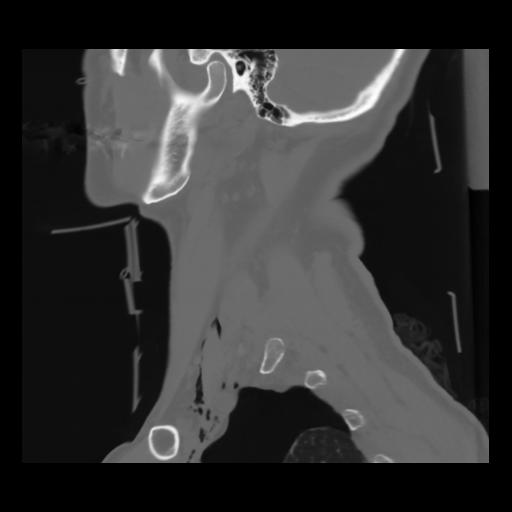

14 P.BLANDAS,,Sagittal,2.000,P.BLANDAS,Sagittal,